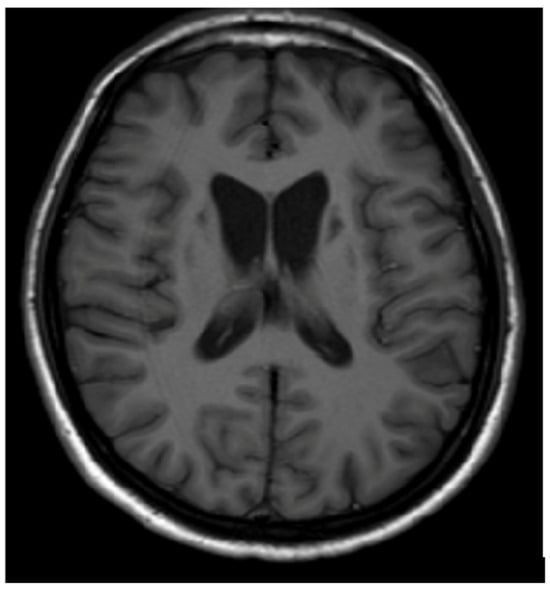

3.1. Classical Brain MRI Examination in WD Patients